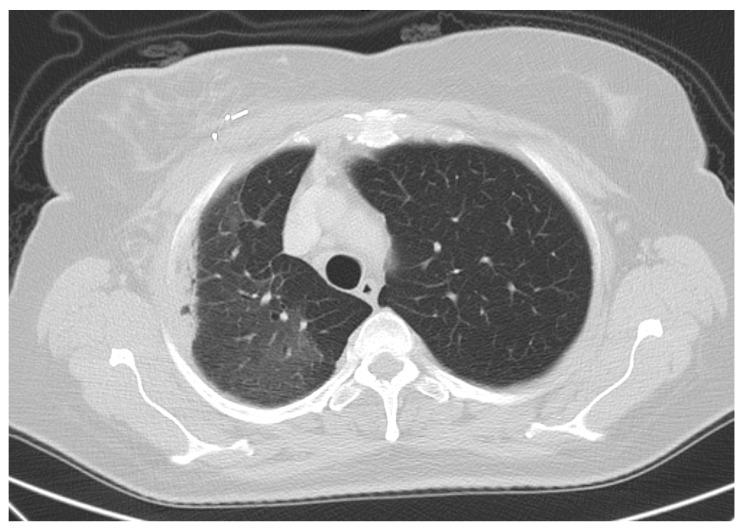

In order to evaluate the risk for radiation-associated symptomatic pneumonitis in a prospective external beam accelerated partial breast irradiation (APBI) trial, between 2011 and 2021, 170 patients with early stage breast cancer were enclosed in the trial. Patients were eligible for study participation if they had a histologically confirmed breast cancer or an exclusive ductal carcinoma in situ (DCIS), a tumor size ≤3 cm, free safety margins ≥2 mm, no involved axillary lymph nodes, tumor bed clips, and were ≥50 years old. Patients received APBI with 38 Gy with 10 fractions in 10 consecutive working days. The trial was registered at the German Clinical Trials Registry, DRKS-ID: DRKS00004417. Median follow-up was 56 (1−129) months. Ipsilateral lung MLD, V20, and V30 were 4.3 ± 1.4 Gy, 3.0 ± 2.0%, and 1.0 ± 1.0%, respectively. Radiogenic pneumonitis grade 2 appeared in 1/170 (0.6%) patients two months after radiotherapy. Ipsilateral MLD, V20, and V30 were 6.1 Gy, 7, and 3% in this patient. Additionally, individual radiosensitivity was increased in this specific patient. Compared to WBI, APBI leads to lower lung doses. Using APBI, the risk of symptomatic radiogenic pneumonitis is very low and may be limited, with an ipsilateral V20 < 3% to very exceptional cases associated with innate risk factors with an increased radiation susceptibility.